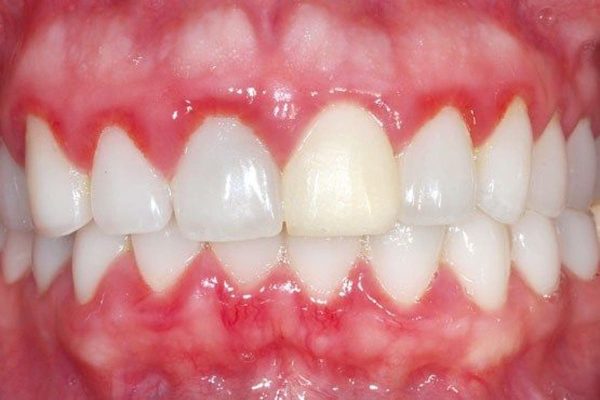

1. Bleeding Gums

Bleeding when brushing or flossing is often the first warning sign of gum inflammation (gingivitis).

Healthy gums should never bleed easily.

2. Red or Swollen Gums

Gums may appear redder and puffier than usual due to bacterial irritation.

This inflammation indicates your immune system is responding to infection.